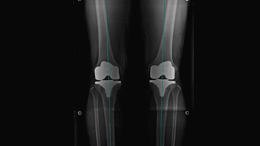

무릎인공관절치환술

• 그림